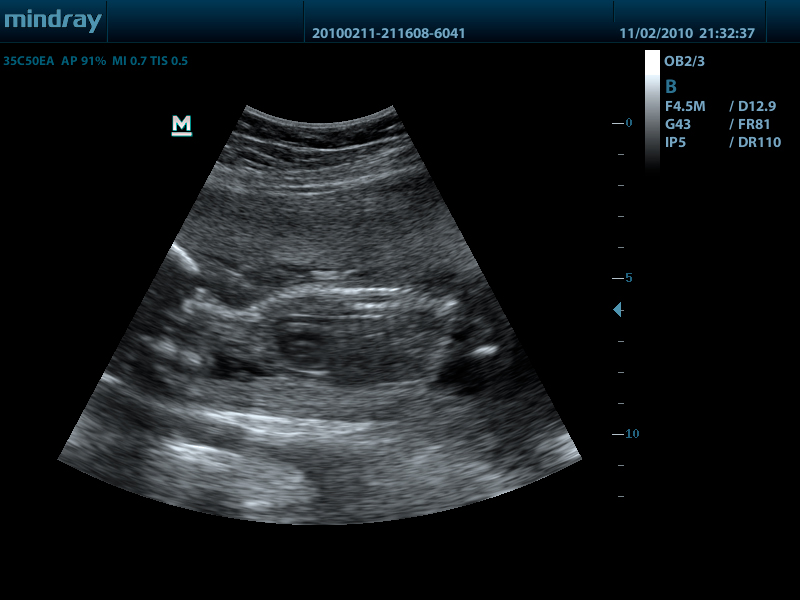

- Конвексный датчик 35C50EA, 1.7 - 6.0 МГц, радиус кривизны 50 мм